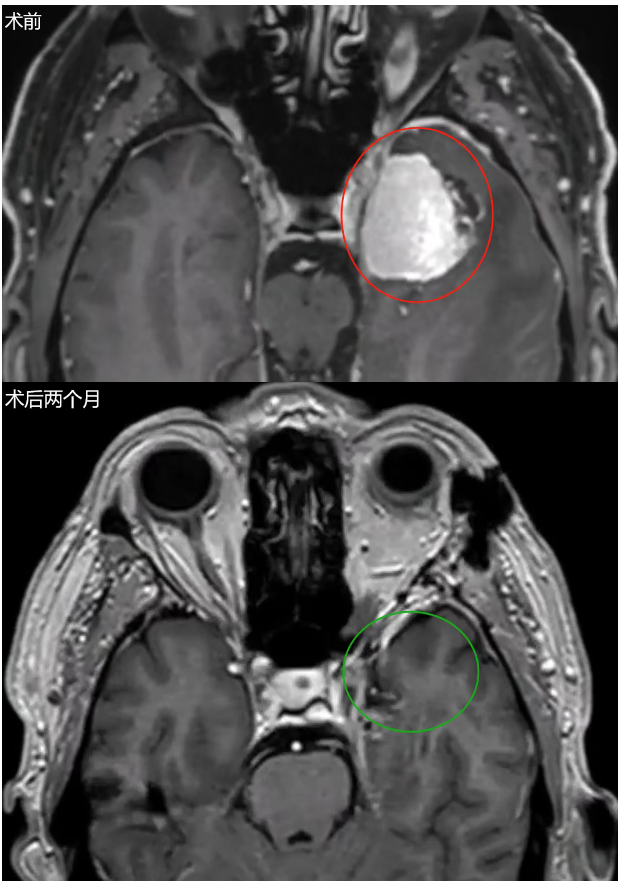

41岁女性,检查发现巨大无功能垂体腺瘤,在外院进行了手术,术后辅助放疗以治疗右侧海绵窦内小残余肿瘤的进展。完成放疗一年后,患者出现右侧动眼神经麻痹,MRI显示右侧海绵窦内肿瘤复发。

▼术前肿瘤持续生长进入海绵窦

INC福教授采用经鼻内镜手术,然后通过移除海绵窦颈内动脉前段上的骨质进行外侧扩大术野。术后磁共振成像(MRI)证实肿瘤肉眼全切。术后,动眼神经麻痹缓解,术后恢复顺利,病理证实为垂体腺瘤。三年后,随访影像显示肿瘤未再生长。

▼术后MR患者动眼神经麻痹消退,影像学检查术后3年无复发。